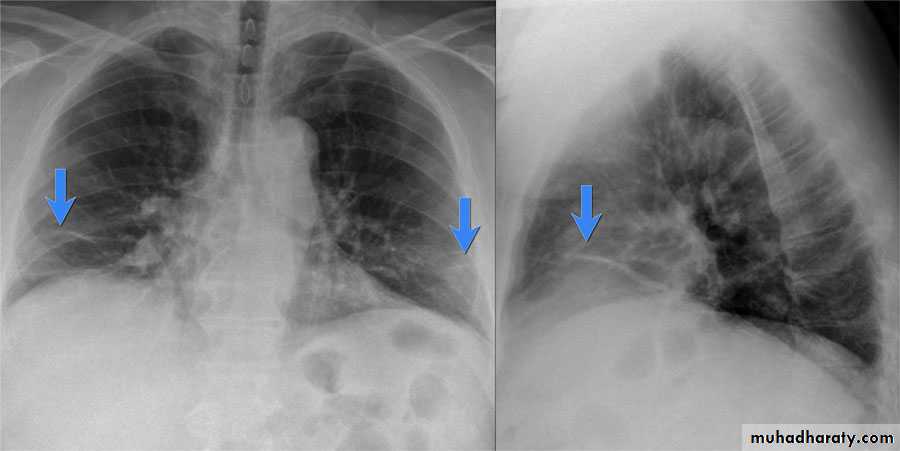

Severe dyspnea with shock